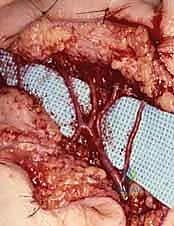

Flatt Digital Sympathectomy Technique

The Flatt Digital Sympathectomy is the cornerstone procedure for medically refractory Raynaud's phenomenon with patent inflow. The objective is the precise mechanical ablation of the sympathetic nerve fibers traveling within the arterial adventitia. Under high magnification, the common digital arteries and their proper digital branches are identified as they emerge from beneath the superficial palmar arch.

The first critical step is the isolation of the digital artery from the adjacent proper digital nerve. These structures are intimately bound by delicate fascial bands. Using fine micro-forceps and micro-scissors, the surgeon meticulously separates the artery from the nerve over a distance of 1.0 to 2.0 cm. Extreme vigilance is maintained to avoid any traction or direct trauma to the nerve, which could precipitate a painful postoperative neuroma.

Once the artery is isolated, the adventitial stripping commences. The surgeon stabilizes the arterial wall with one set of non-toothed jeweler's forceps. With a second set of forceps, the thin, translucent outer adventitial layer is grasped. Using a highly controlled, peeling motion—akin to removing the thin skin from a grape—the adventitia is stripped circumferentially from the underlying muscularis media.

As the adventitia is removed, the visual appearance of the artery changes dramatically; it transitions from a slightly opaque, tethered vessel to a smooth, highly translucent, and often visibly dilated conduit. This visual cue is the hallmark of a successful sympathectomy.

Concurrently, the surgeon must identify and sharply divide any microscopic tethering branches or fine neural connections bridging the proper digital nerve and the arterial wall, as these frequently carry aberrant sympathetic fibers.

Radical Digital Sympathectomy and Microvascular Considerations

In patients presenting with profound, widespread vasospasm or severe ischemic ulcerations involving multiple digits, a localized Flatt sympathectomy may be insufficient. In these severe cohorts, a radical or extensive digital sympathectomy is indicated. This highly aggressive approach involves skeletonizing the arterial tree from the distal forearm down to the proper digital arteries.

The dissection begins proximally, stripping the adventitia from the distal radial and ulnar arteries as they enter the wrist. The superficial palmar arch is entirely exposed and denuded of its adventitial layer.

This extensive dissection requires navigating the complex neural anatomy of the palm, particularly the branches of the median and ulnar nerves, ensuring they are gently retracted and protected.

If, during the exploration, an area of fixed occlusion or a thrombosed aneurysm (such as in hypothenar hammer syndrome) is encountered, the procedure transitions from sympathectomy to microvascular reconstruction. The diseased arterial segment is resected until healthy, pulsatile intima is visualized proximally and distally. An autologous reversed saphenous vein graft is harvested, prepared, and interposed into the defect. End-to-end microvascular anastomoses are performed using 8-0 or 9-0 non-absorbable monofilament sutures under the microscope, ensuring precise intimal coaptation to prevent turbulent flow and re-thrombosis.

Upon completion of either sympathectomy or bypass, the tourniquet is deflated. The surgeon observes the extremity for the return of brisk capillary refill and the resolution of pallor. Topical vasodilators, such as papaverine or lidocaine, may be applied directly to the vessels to counteract any mechanically induced vasospasm. Meticulous hemostasis is achieved using bipolar electrocautery before the skin flaps are loosely approximated to accommodate postoperative edema.